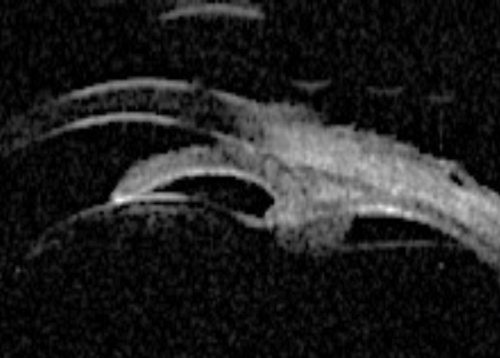

Pupillary block accounts for the majority of cases of primary angle closure. In pupil block, pressure builds up from behind the iris and pushes it anteriorly. UBM can be used to demonstrate that the iris assumes a convex profile due to these pressure differences and this convexity is noted over the entire iris length. Consequent to this, iridocorneal contact results, and the angle is closed (Figure 1).

Figure 1a: Pupil block profile characterised by a convexed profile of the peripheral iris and irido lenticular contact.